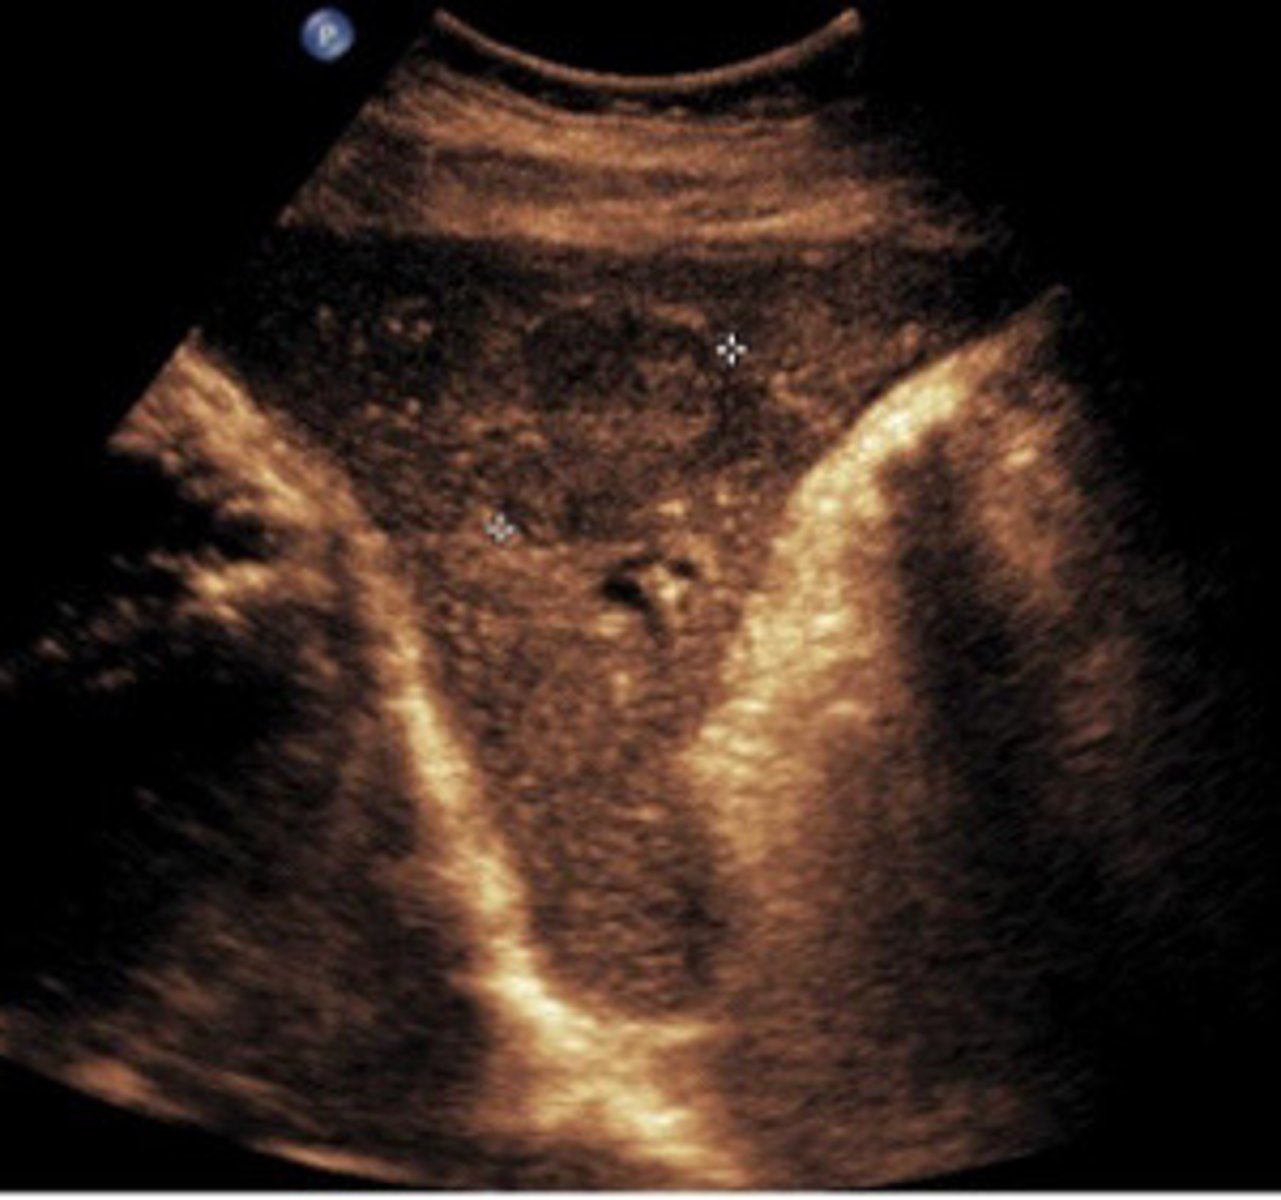

FNH

What does this image show

FNH (seen better with colour map)

What are the arrows pointing to